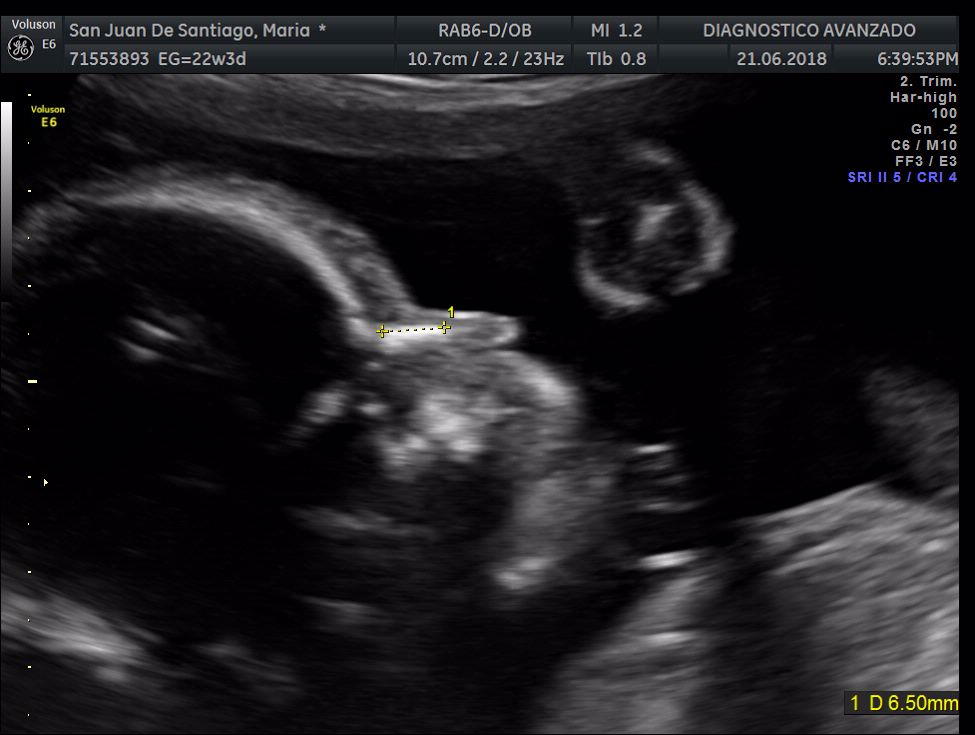

¡Hola a todos! Hoy hemos ido a hacer la tradicional ecografía 3D de la niña, os dejamos todo el material (aunque es un poco demasiado).